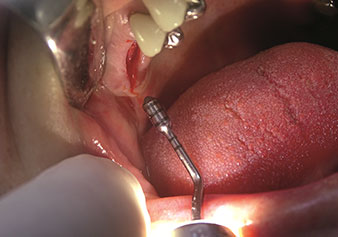

One application, which is often underestimated is the atraumatic extraction of tooth roots or root fragments in the scope of alveolar management. The fine periotomes, which are currently available in two versions (EX1 and EX2 from W&H), can also be used to remove teeth which have previously undergone special endodontic treatment or ankylosed roots with ease. This results in extraction alveoli where both the hard and soft tissue are fully intact as it is generally possible to avoid reflection.

This establishes the optimal basis for subsequent or immediate implant treatment (Figures 1 and 2 included with the kind permission of Dr Torsten Conrad, Bingen a. Rhein).

Photo: © Dr Torsten Conrad (Bingen am Rhein)